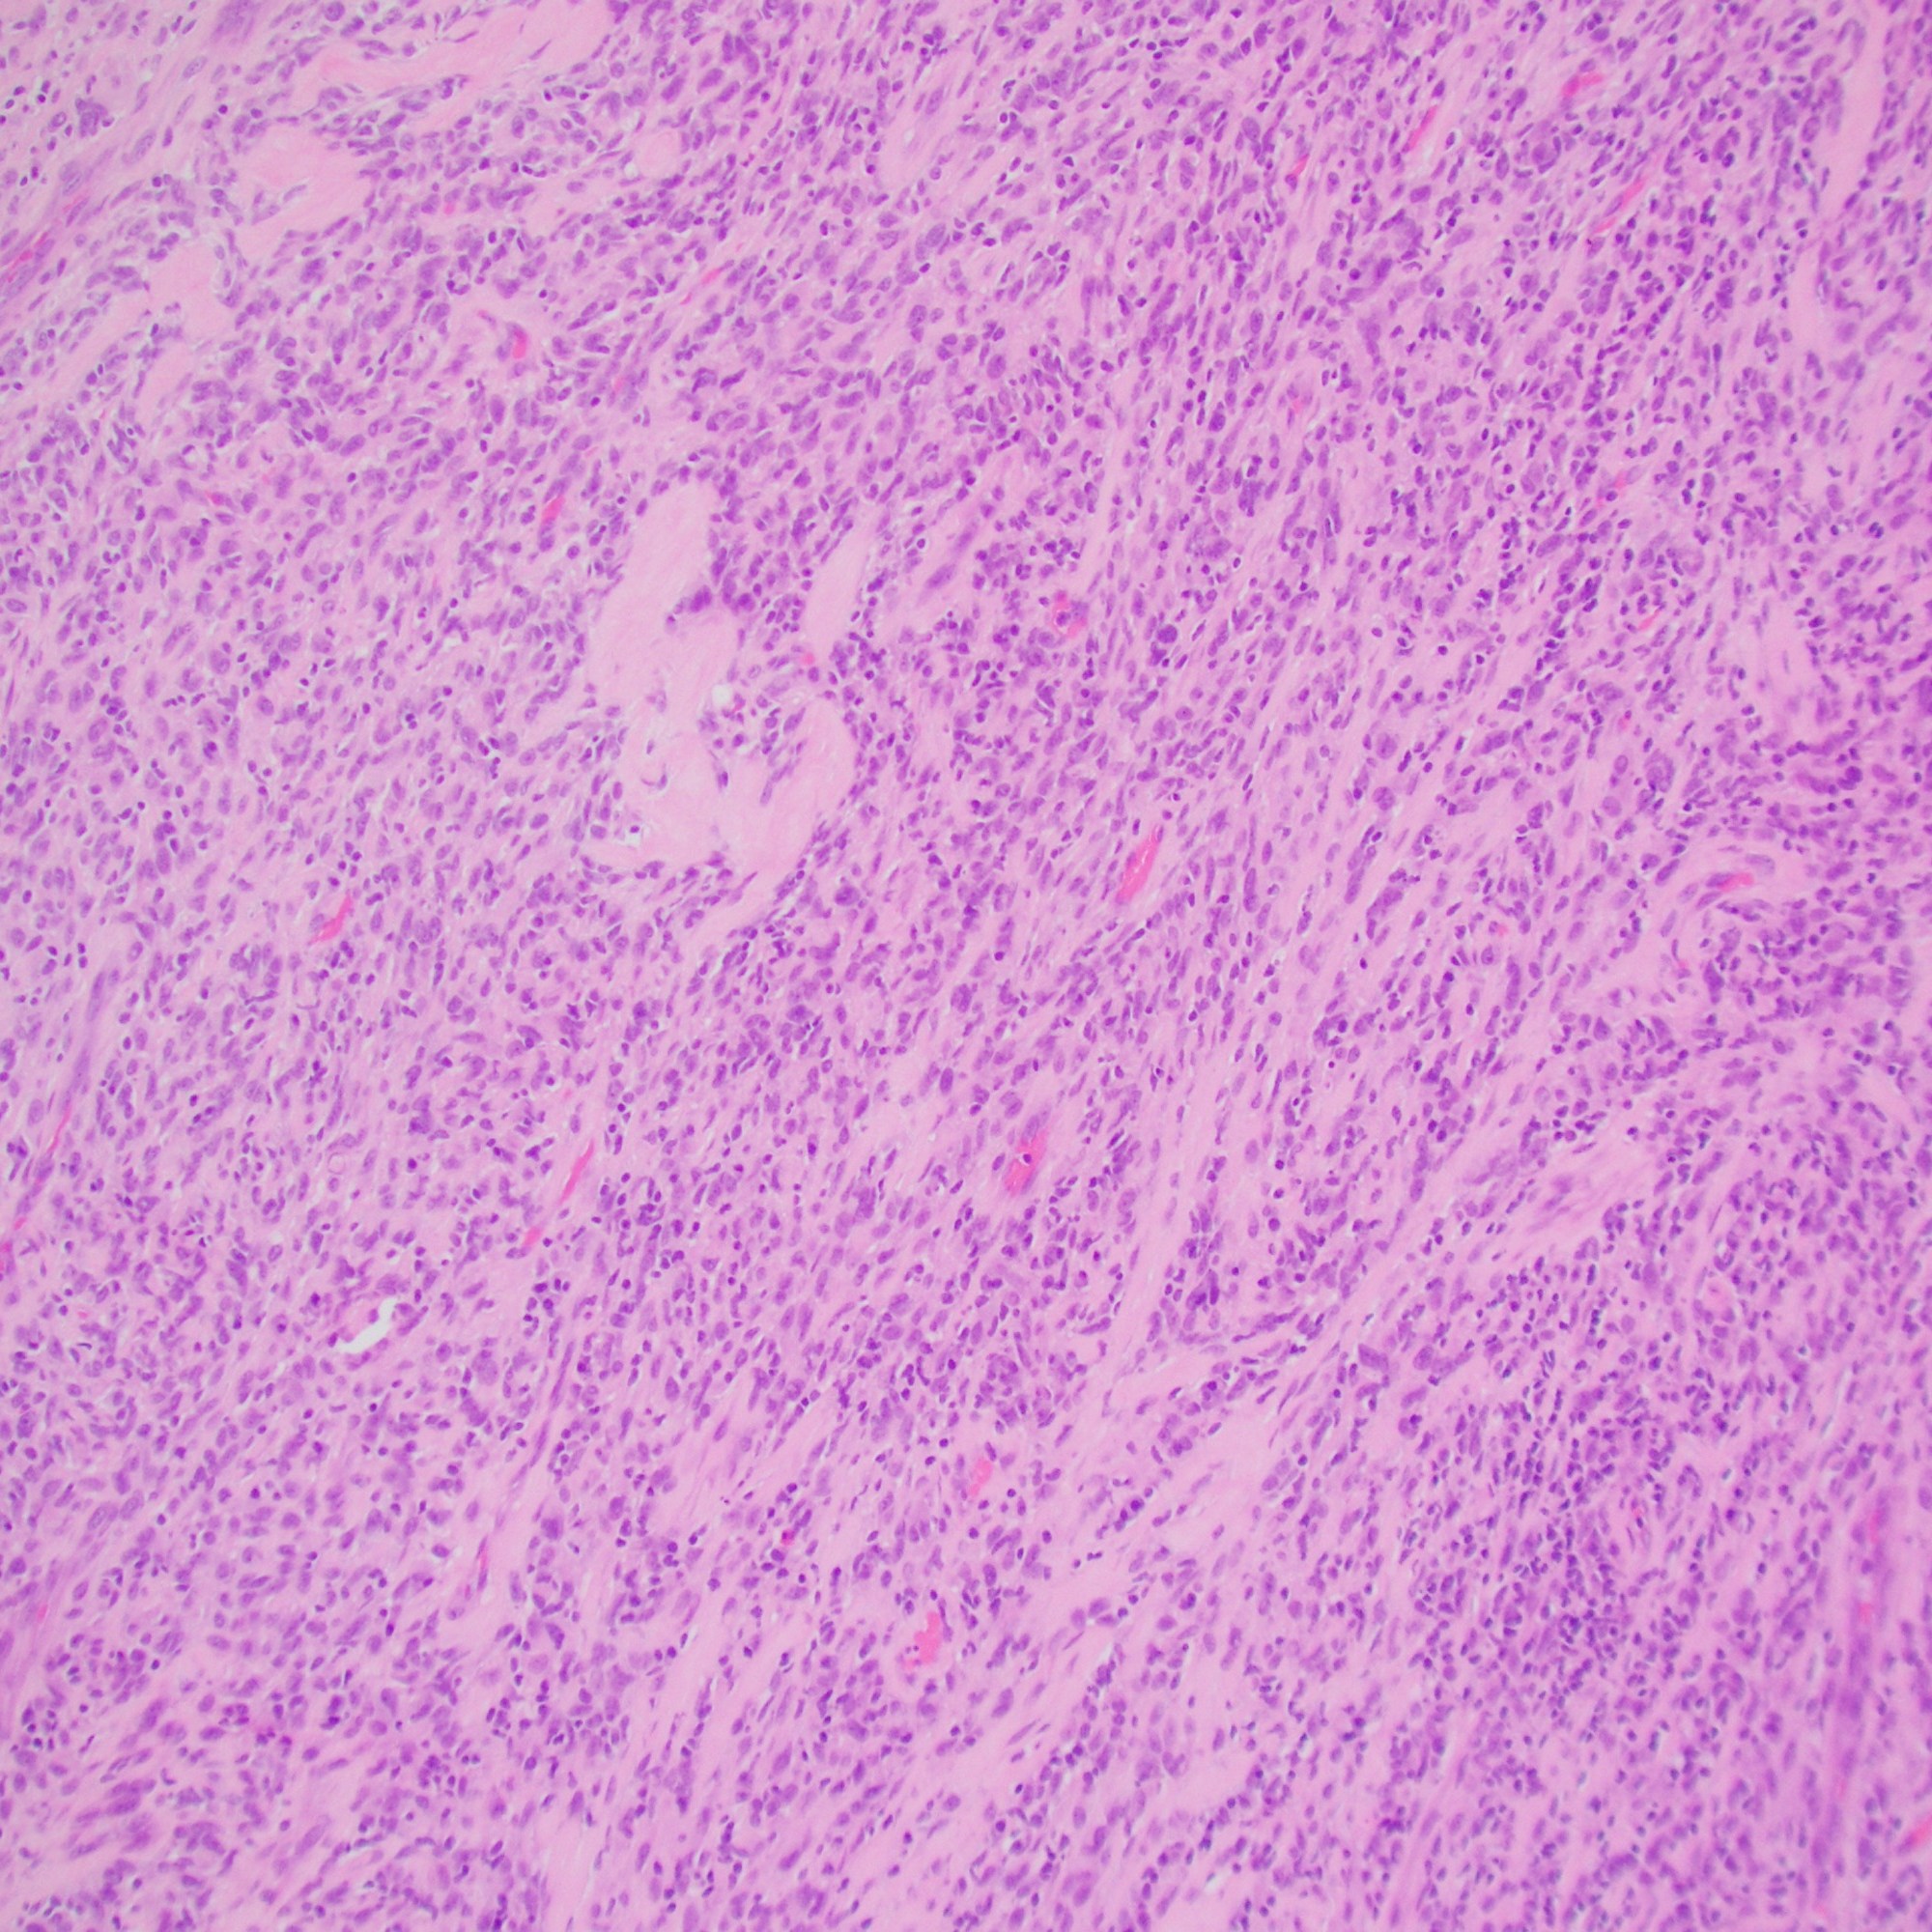

- Monotonous, mild nuclear pleomorphism

- Chromatin pattern more coarse and more prominent nucleoli than Ewing sarcoma (EwS)

- Site:

- Deep soft tissue of the limbs or trunk > head and neck, retroperitoneum, and pelvis; 10% arise in viscera (kidney, gastrointestinal tract, and brain)

- CIC::DUX4 fusion

- Present in 95% of cases

- Either a t(4;19)(q35;q13) or a t(10;19)(q26;q13)

- Less common partner genes: FOXO4, LEUTX, NUTM1, and NUTM2A

- IHC:

- Positive for CD99 (diffuse or patchy, membranous and/or cytoplasmic)

- WT-1 (nuclear with or without cytoplasmic in up to 95% of cases)

- ETV4

- Aggressive tumours, with frequent metastases and a poor outcome; EwS therapy less effective